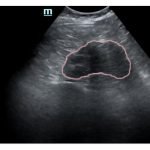

Bedside ultrasound was performed and demonstrated a hypoechoic area within the left kidney (images not shown). The non-contrast computed tomography (CT) of the abdomen and pelvis shows a significantly enlarged left kidney and a region of high-attenuation encapsulating the left kidney, concerning for acute hemorrhage.